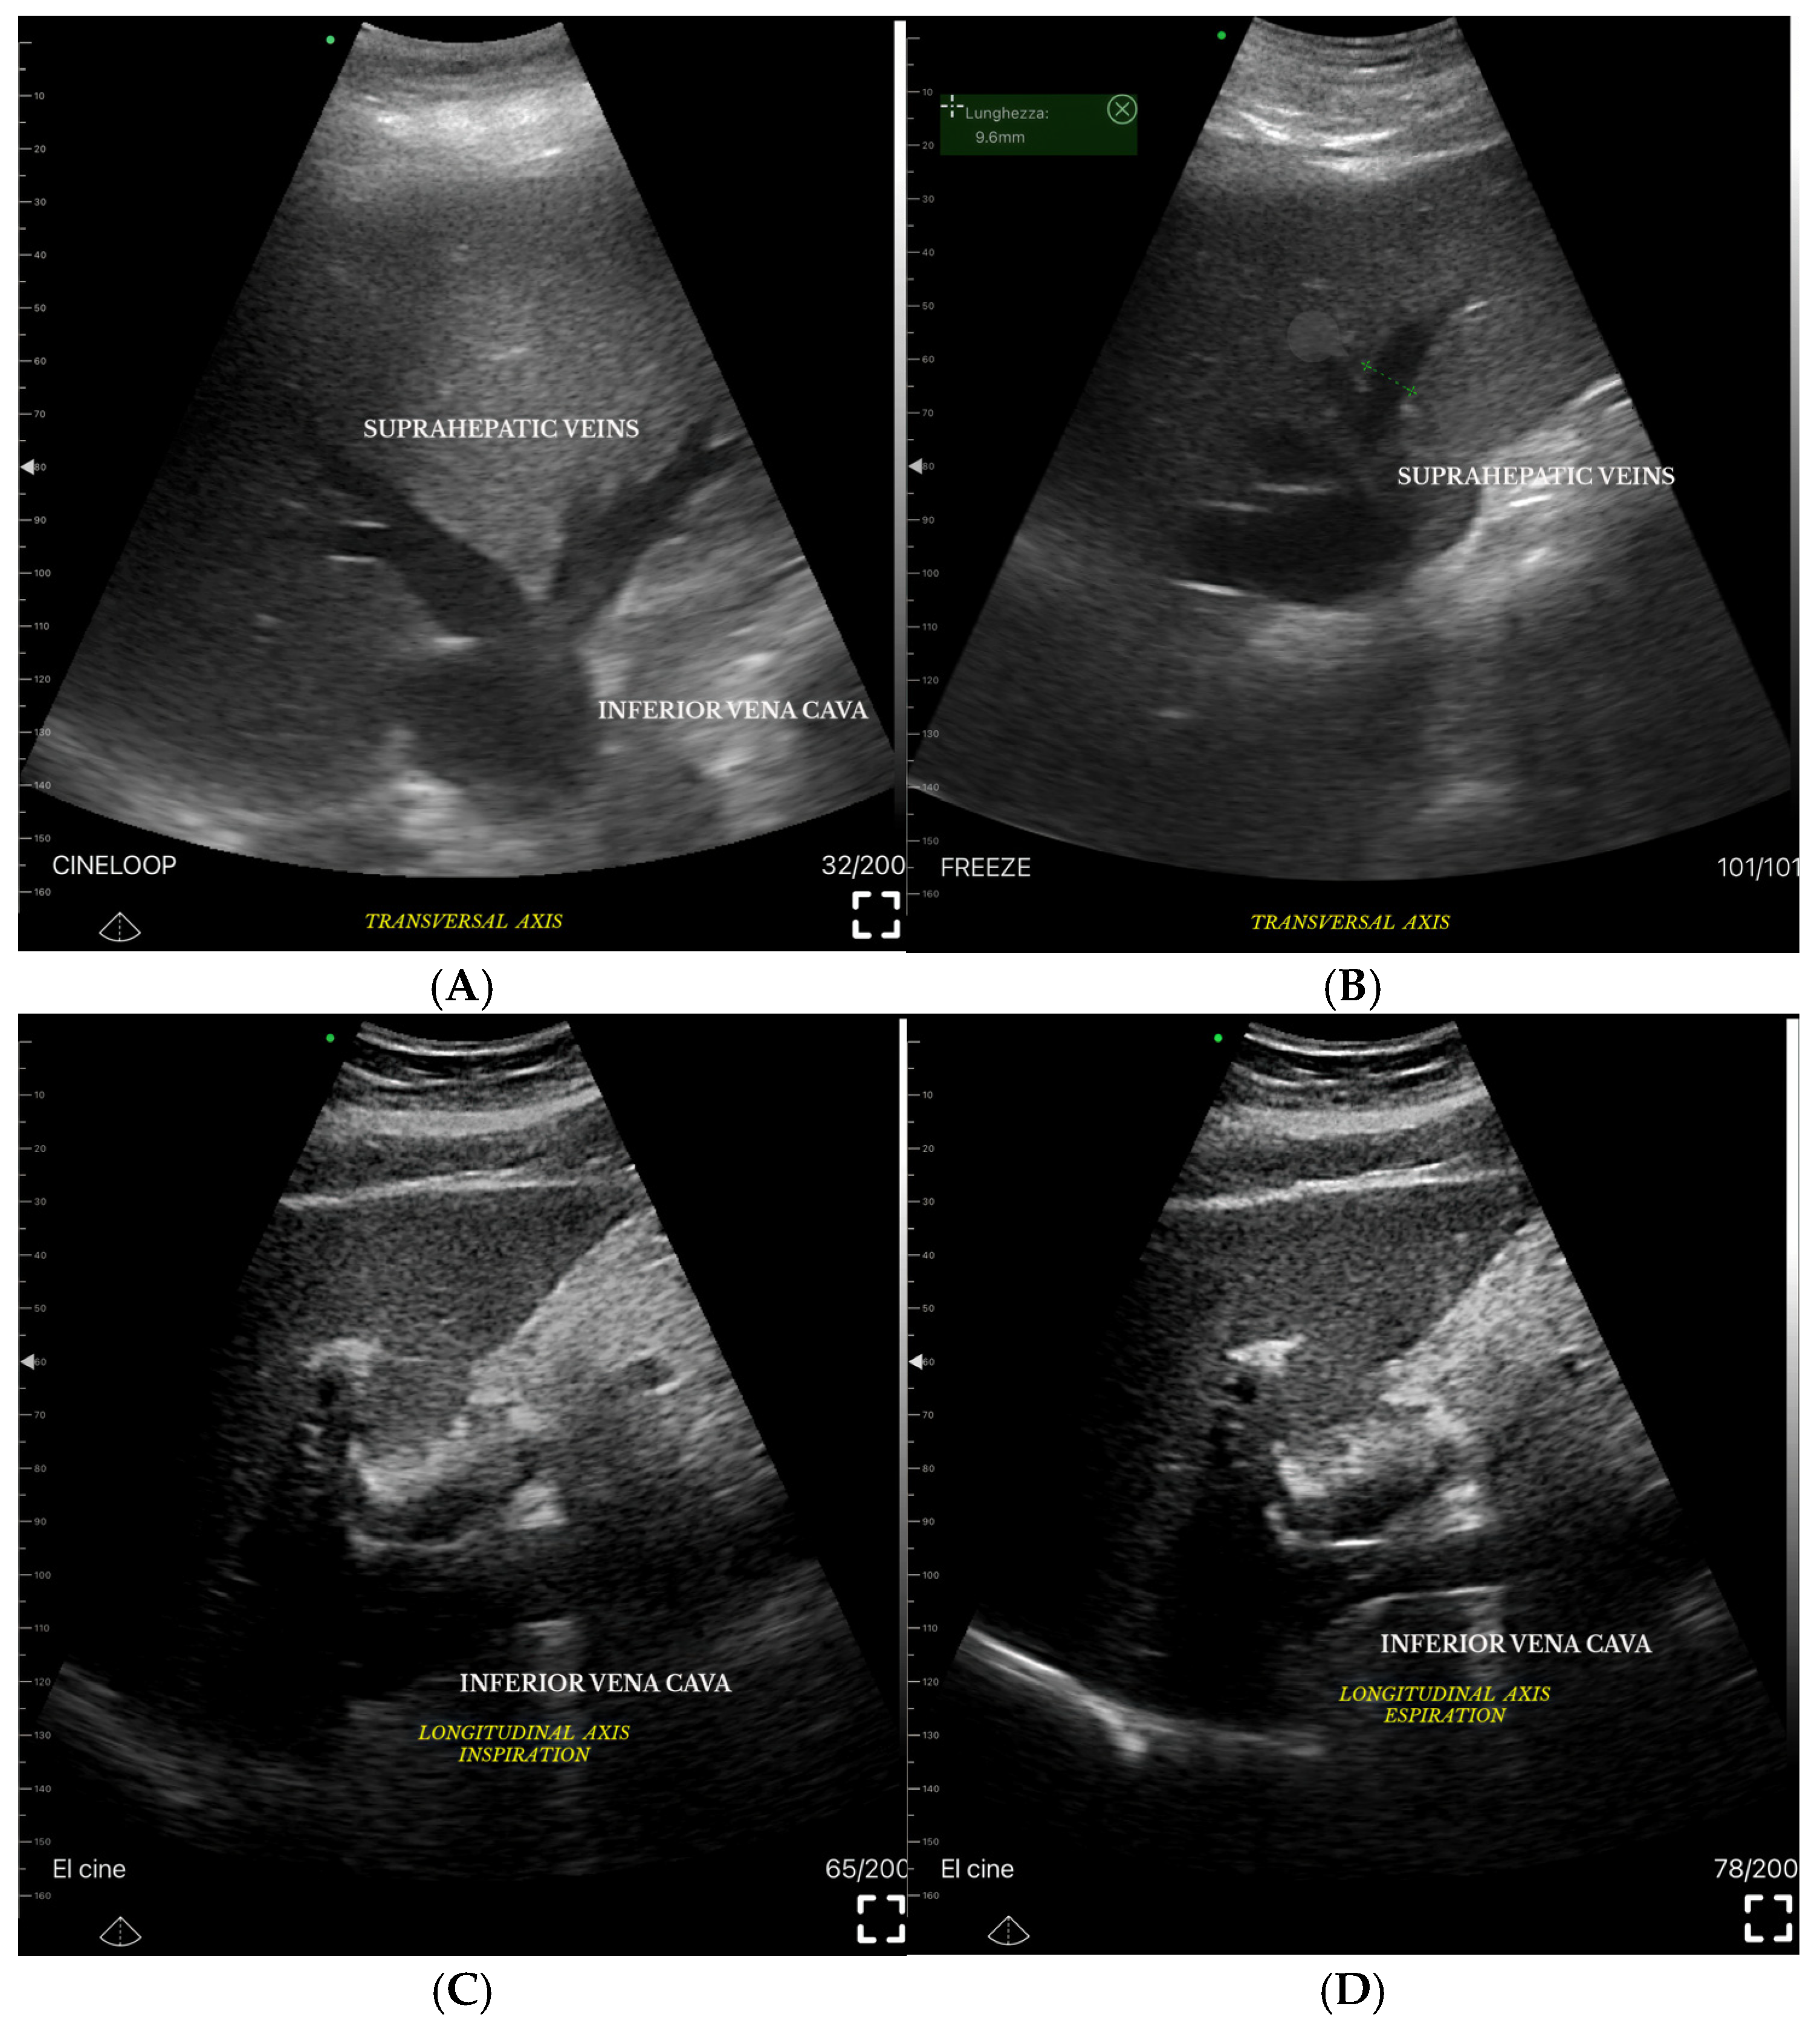

- B-Mode Parameters: Bowel wall thickness, inferior vena cava (IVC) diameter and collapsibility, hepatic vein dilation.

- Grading Venous Congestion: Venous congestion is categorized into grades 0–3 based on waveform alterations, a system known as VExUS (Venous Excess Ultrasound Score) (Figure 14) [63]. This grading system provides a practical method for assessing the severity of venous congestion in clinical settings (Figure 15).